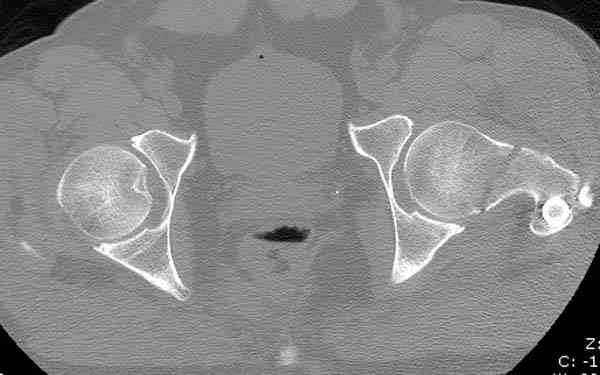

Кроме обязательных ренгенологических снимков тазобедренного сустава, при подозрении на перелом шейки рекомендуем Компьютерную Томографию.

Здесь представлены снимки больного 65 лет, поступившего с диагнозом перелом

бедра после автоаварии.

В первый же день произведено антеградное штифтованием DePuy Trochanteric Nail.

На второй день (7) обнаружен пропущенный перелом,

сделаны Компьютерная Томограмма